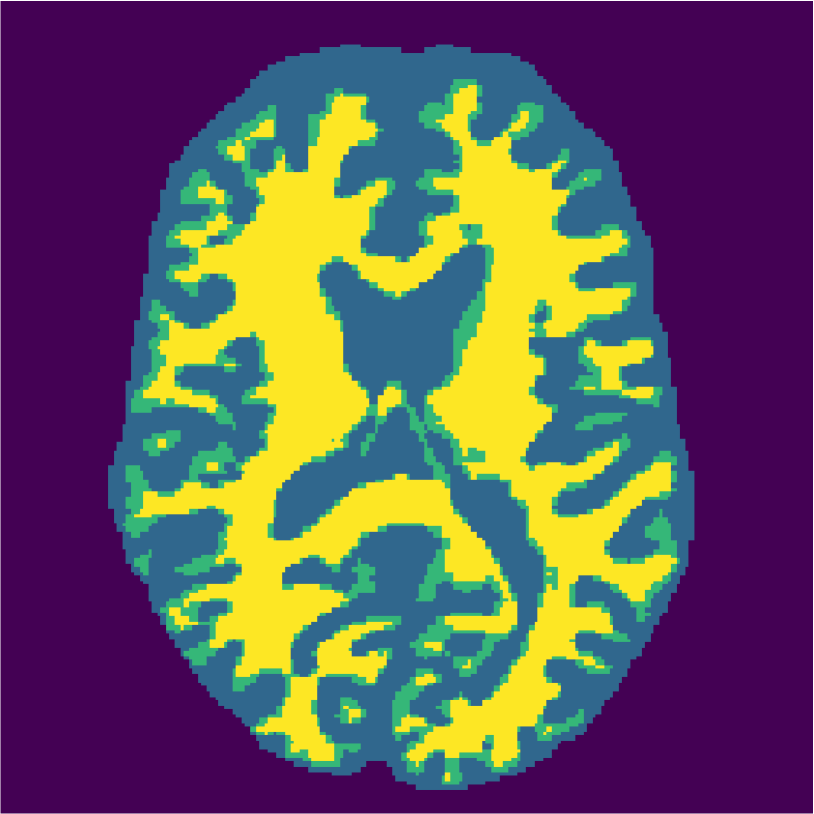

Examples of the segmentation results on one of the target test images are shown in Figure 8 for experiment 2.1, Figure 9 for experiment 2.2, and Figure 10 for experiment 2.3. Examples are shown after using 1 target patch per tissue for training, and after using 100 target patches per tissue for training. The results show that only the mrai-net classifier is able to predict a segmentation that approaches the ground truth with only 1 target patch per tissue for training (error for experiment 2.1 = 0.269, experiment 2.2 = 0.403, experiment 2.3 = 0.320), while the source and target classifiers cannot (source error for experiment 2.1 = 0.667, experiment 2.2 = 0.653, experiment 2.3 = 0.435; target error for experiment 2.1: 0.591, experiment 2.2: 0.614, experiment 2.3 = 0.596). After using 100 patches the source and target classifiers can predict a gross segmentation of WM, GM and CSF (source error for experiment 2.1 = 0.213, experiment 2.2 = 0.384, experiment 2.3 = 0.363; target error for experiment 2.1: 0.205, experiment 2.2: 0.368, experiment 2.3 = 0.368), but the mrai-net classifier prediction shows more details and a lower tissue classification error (error for experiment 2.1 = 0.111, experiment 2.2 = 0.276, experiment 2.3 = 0.284).

2.3) Experiment on 3.0T simulated data and 3.0T real data (Source: Brainweb3.0T, Target: MRBrainS).